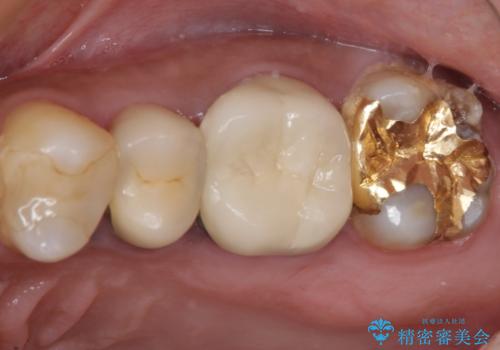

食事で痛む 神経を極力残した虫歯治療